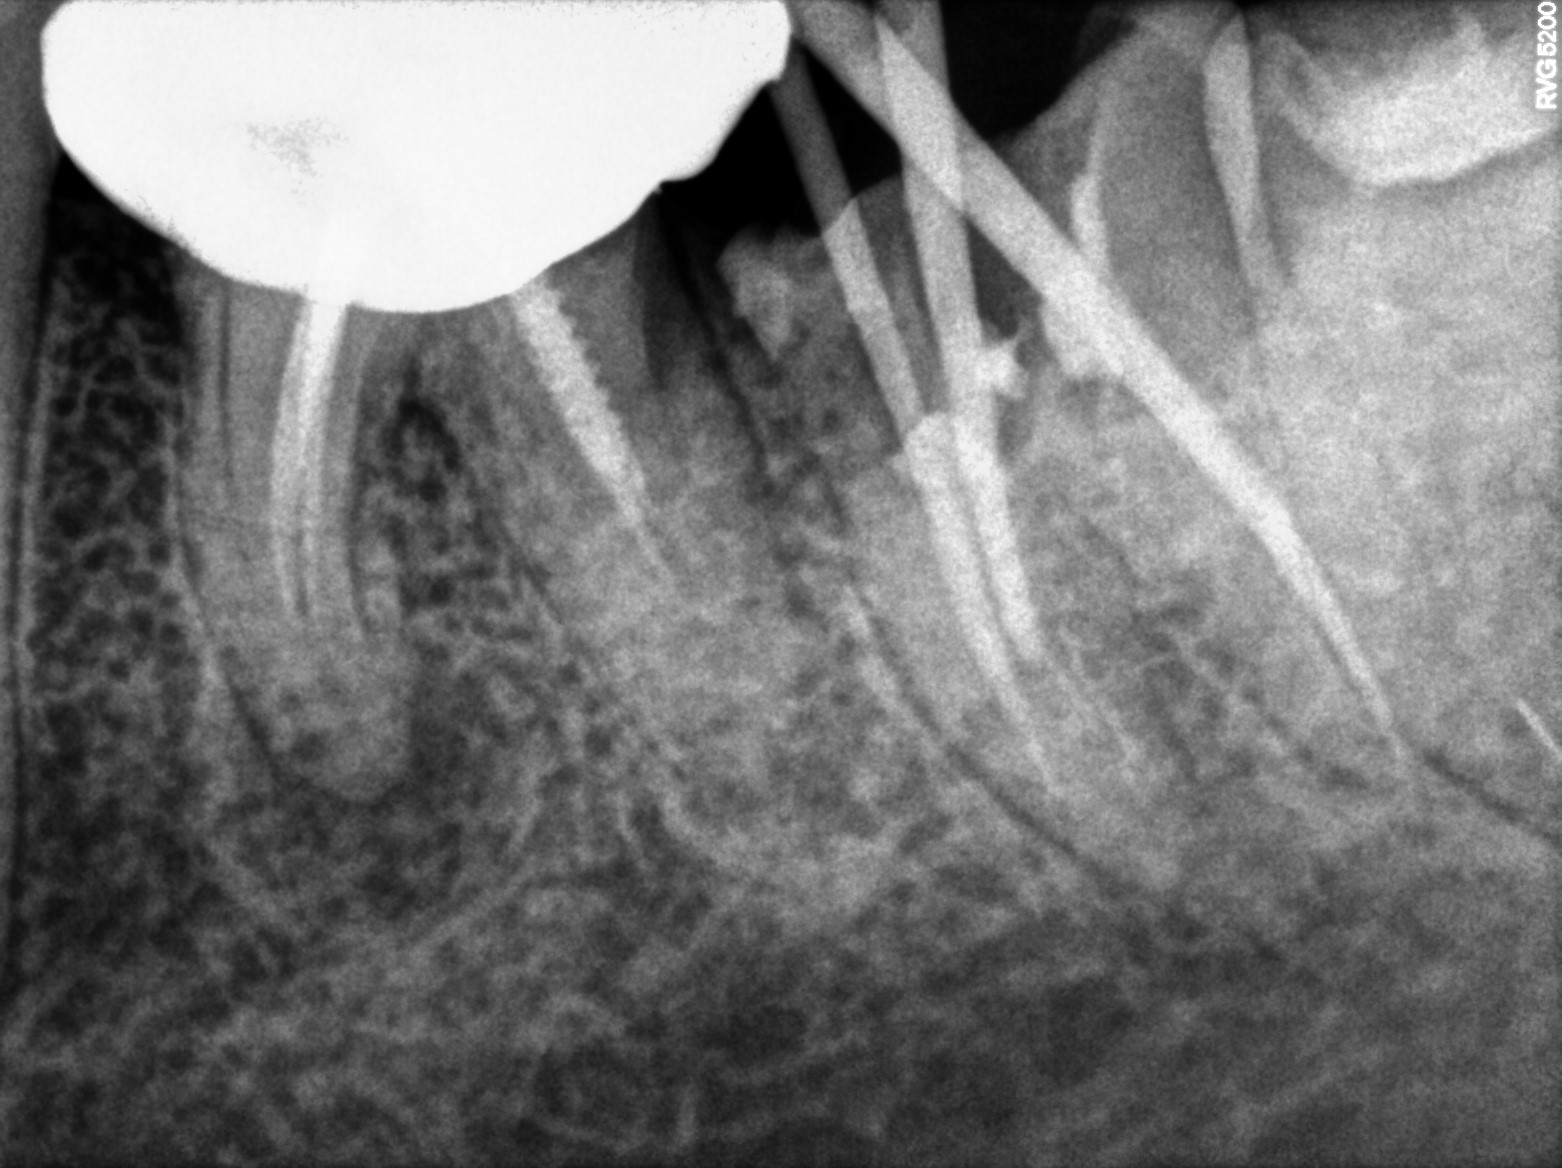

Dental Radiographs FHIR: DocumentReference · LOINC 24641-7

R55.jpg

24641-7